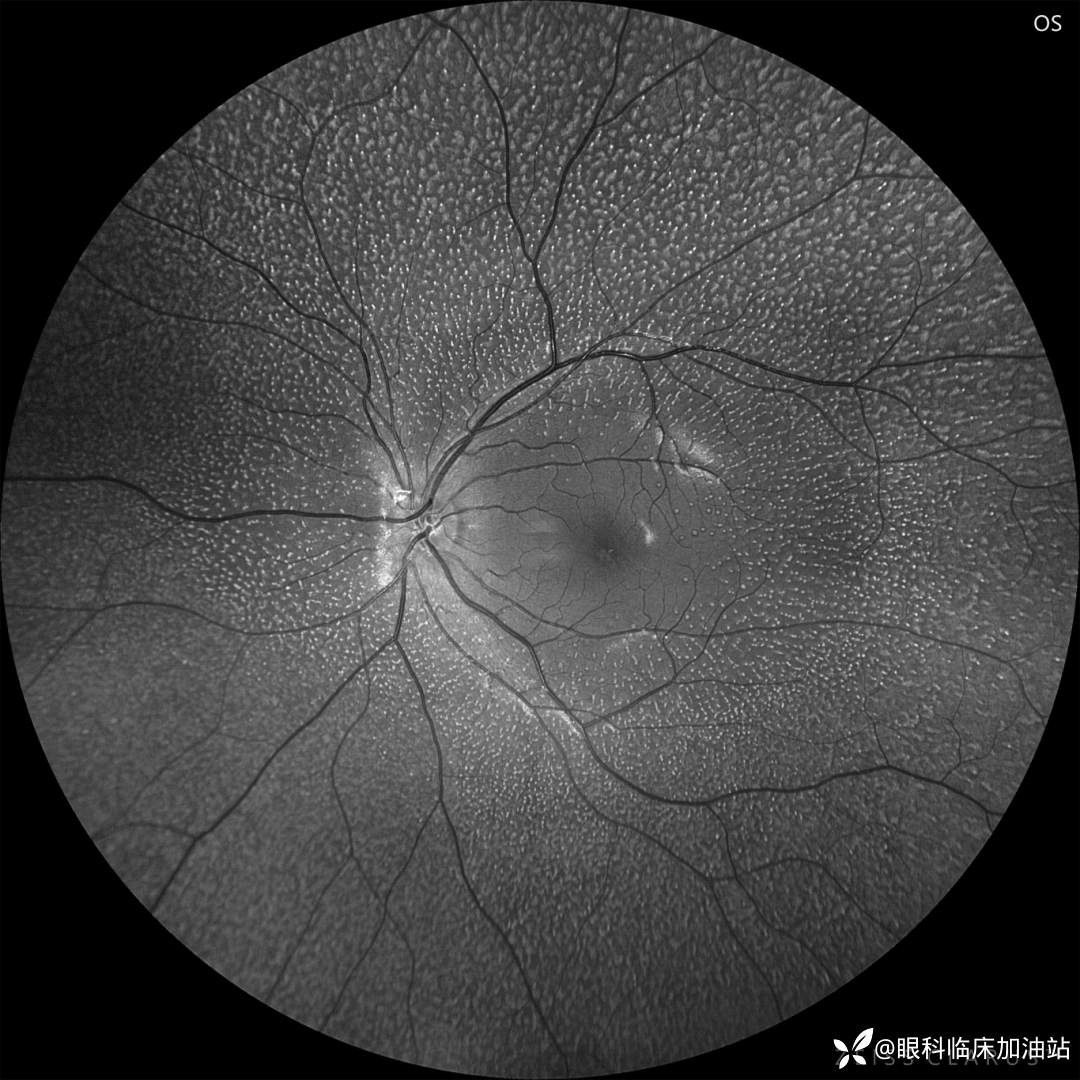

左眼